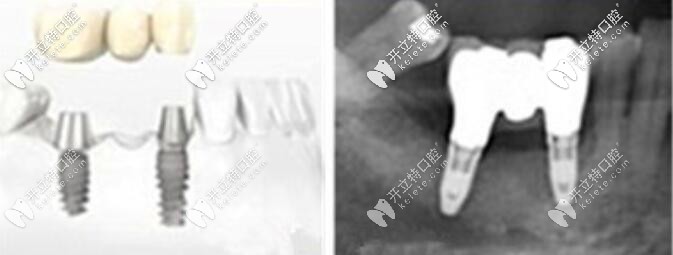

這是一個缺三種2的案例圖↓↓↓

這是一個缺三顆牙種2顆植體的案例圖